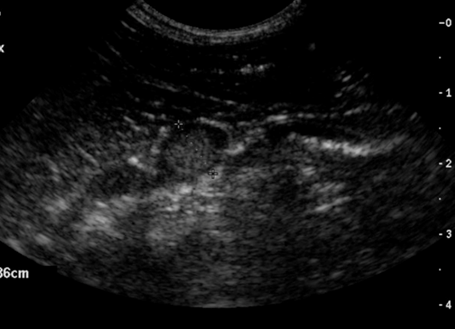

Echografisch beeld van de rechterbijnier toont geen normale bijnier structuur meer. Er is een grote massa te zien met heterogene structuur. Dit is waarschijnlijk ten gevolge van pheochromocytoom (Devil).